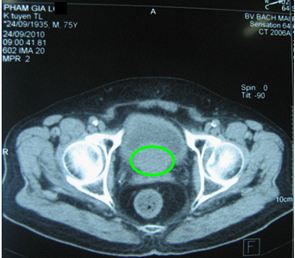

Chụp CT 64 dãy (MSCT) tiểu khung: Tuyến tiền liệt 3 x 4 cm, ước lượng 21g, không có khối khu trú, không ngấm thuốc bất th­ường, không xâm lấn túi tinh và bàng quang.

Tr­ước điều trị

Tiểu tiện khó, tiểu máu

TTL: 6 x 5,1 cm; 86 g

PSA: 145 ng/ml